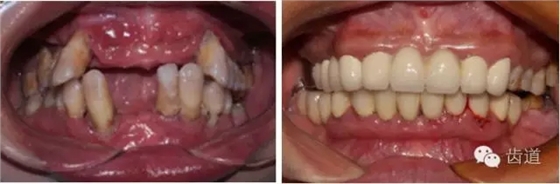

1、口腔衛(wèi)生狀況及局部刺激物(牙菌斑、牙石,不良修復(fù)體)

牙石及不良修復(fù)體

2、牙齦

(顏色、形狀、質(zhì)地、退縮、BOP、PD、附著齦)